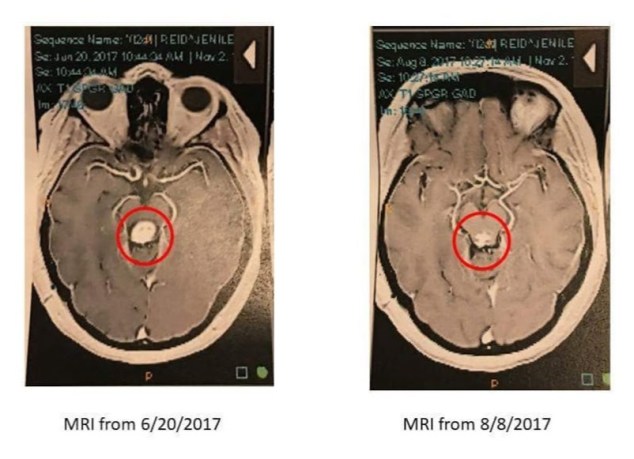

Jenilee started chemo to put an end to this brain tumor that’s been giving her hell for a while. Keenan finally got his CPA certificate in the mail. Chompers and I bonded in a whole new way and now she’s basically my favorite puppy ever.

August & September… Um, let’s just jump to seeing the Beauty & The Beast ballet with some pretty amazing friends. That and the fact that Jenilee’s tumor was shrinking was just about the only good parts of these 2 months. I was SUPER excited to see that my Nonnie had made it to her 77th birthday! The in-loves came to visit too. I love seeing them.

November was a rough one. We lost my dear Nonnie on the 17th. Jenilee was up to 5 chemo treatments! I was well on my way to start the process to my gastric sleeve surgery.

December. We had my Nonnie’s “Celebration Of Life” to kick off this month. Keenan got sleeved on the 11th. I went to the Nutcracker ballet and it was easily the most magical night of the year. All 4 Christmas gatherings were completed before New Year’s Eve. (Guys, this never happens.) It was wonderful! Jen completed one type of chemotherapy and will be starting a new type next week.